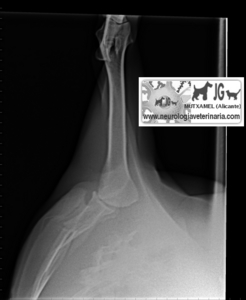

Radiografía del mismo paciente en el momento del accidente (nótese el neumotórax consecuente a la fractura de escápula) |

Nótese la perforación de la caja torácica |

Neumotórax |